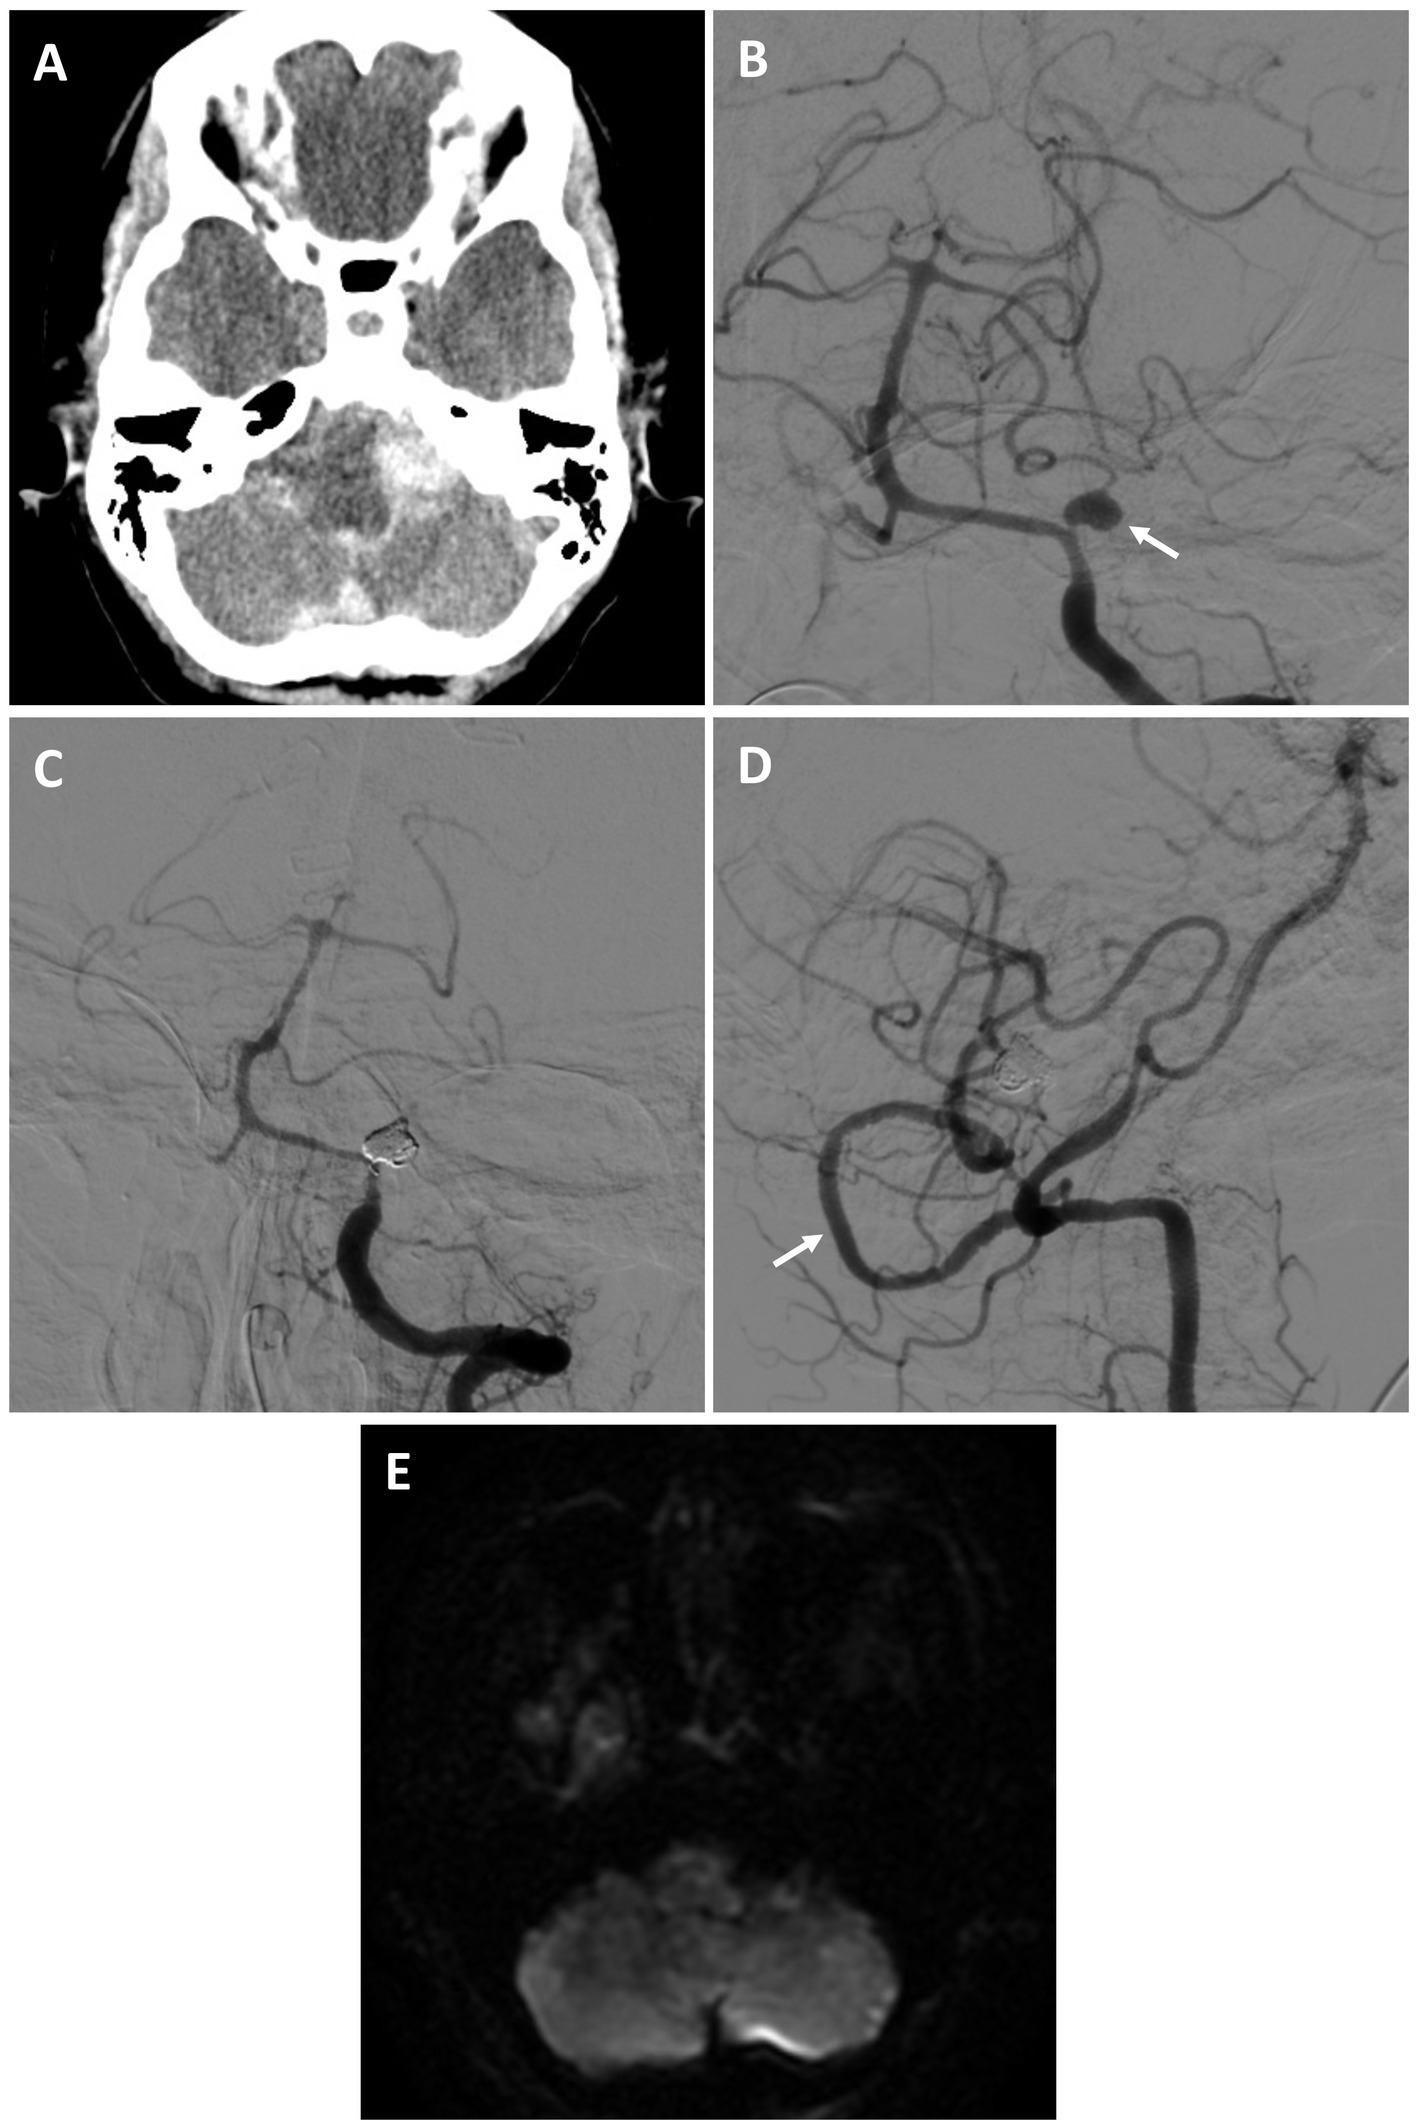

A 59-year-old female who was recovering at an outside hospital from a perforated diverticulum experienced a severe acute headache followed by a seizure and was found to have diffuse subarachnoid hemorrhage (SAH) and obstructive hydrocephalus from a ruptured left proximal PICA fusiform aneurysm (Hunt and Hess 3, Fisher 4) (Figures 2A,B). She was stabilized with an external ventricular drain and transferred to our facility. She was recommended for a combined open revascularization and endovascular aneurysm/vessel occlusion on multidisciplinary review. As the contralateral PICA was not favorable for IC-IC bypass a V3 to left tonsillar PICA bypass using a DLCFA interposition graft was performed after a suboccipital craniotomy and C1 laminectomy. Immediately afterwards, the left PICA aneurysmal segment was internally embolized with coils (Figures 2C,D). She had an uneventful hospital course without complications (Figure 2E). On four-month follow up she was performing all activities of daily living independently.

Figure 2

Patient #7. A 59-year-old female experienced a Hunt and Hess 3, Fisher 4 SAH from a left proximal PICA fusiform aneurysm [(A) axial non-contrast head CT; (B) AP angiogram of the left vertebral artery (arrow highlighting aneurysm)]. She underwent a V3 to PICA bypass using a DLCFA interposition graft, followed by internal PICA aneurysm embolization. She had no strokes and an uneventful recovery. On 4-month follow was performing all activities of daily living independently. Angiogram demonstrating PICA occlusion [(C) AP left vertebral artery injection, and patent bypass (D) lateral right vertebral artery injection (arrow highlights bypass)]. (E) Post-procedural MRI (axial DWI) demonstrated no strokes.